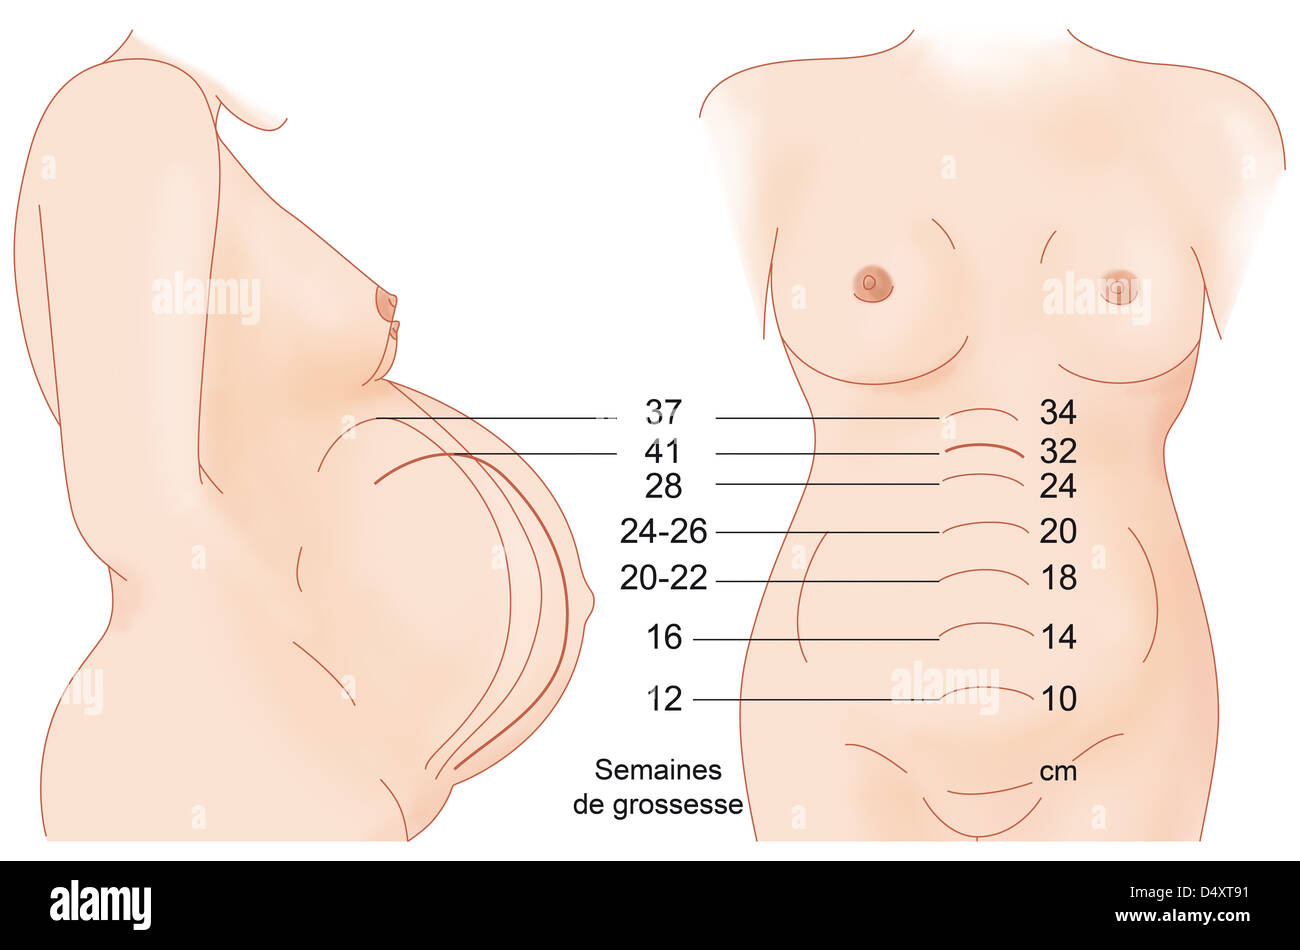

HAUTEUR UTÉRINE Banque D'Imageshttps://www.alamyimages.fr/image-license-details/?v=1https://www.alamyimages.fr/photo-image-hauteur-uterine-54679549.html

HAUTEUR UTÉRINE Banque D'Imageshttps://www.alamyimages.fr/image-license-details/?v=1https://www.alamyimages.fr/photo-image-hauteur-uterine-54679549.htmlRMD4XT91–HAUTEUR UTÉRINE